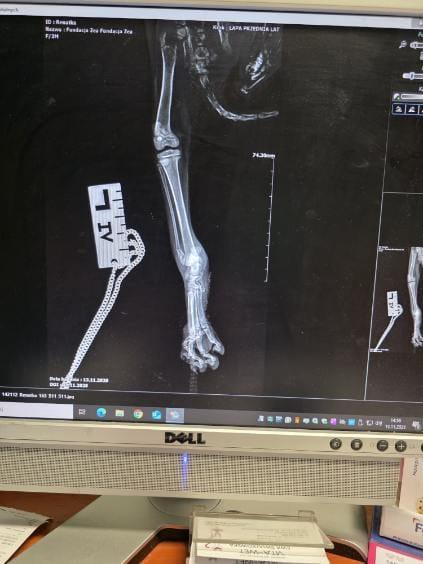

• Days Won

7. Prawdopodobnie będzie amputowana. Na razie malutka jest za słaba, no i te rany ogromne.

8. W środę w okolicach Carrefour w Zamościu zostało znalezione poranione kociątko Malutka Renatka ma ok. 3 mies., waży 1 kg, ma złamane dwie łapki, jedna jest prawdopodobnie do amputacji.

9. W poniedziałek o godz. 14.00 w Lublinie jest zaplanowana operacja Malinki. Założyłam dzisiaj zbiórkę na Ratujemy Zwierzaki, niestety nie mogę jej tutaj pokazać. Bardzo proszę Cioteczki z Fb o udostępnianie.